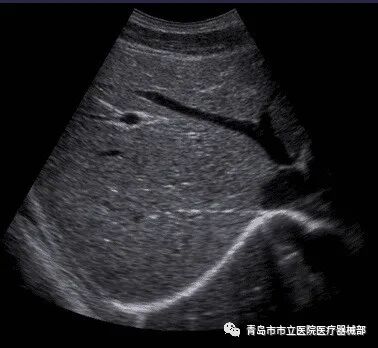

3.2B超(B-mode

B型超声中的B来自于brightness的第一个字母,为辉度图像。其与A超一样,接收不同深度的回声,在声像图中,用辉度(brightness)变化表示回声强度变化,只有产生回声的部位(深度)才有辉度点。发射-接收1次信号,辉度点连成一线,即辉度线(扫描线);1次发射-接收信号后,略微移动探头的位置,再次进行发射-接收信号,重复相同过程,随着探头的移动,相应形成新的辉度线;如此反复,回声源的位置和形态就在声像图中得到显示。

(简述:以亮度的强弱显示组织回波信号的强弱,并转为二维灰度图像。二维断面图像,实时显示组织结构,形象直观。)